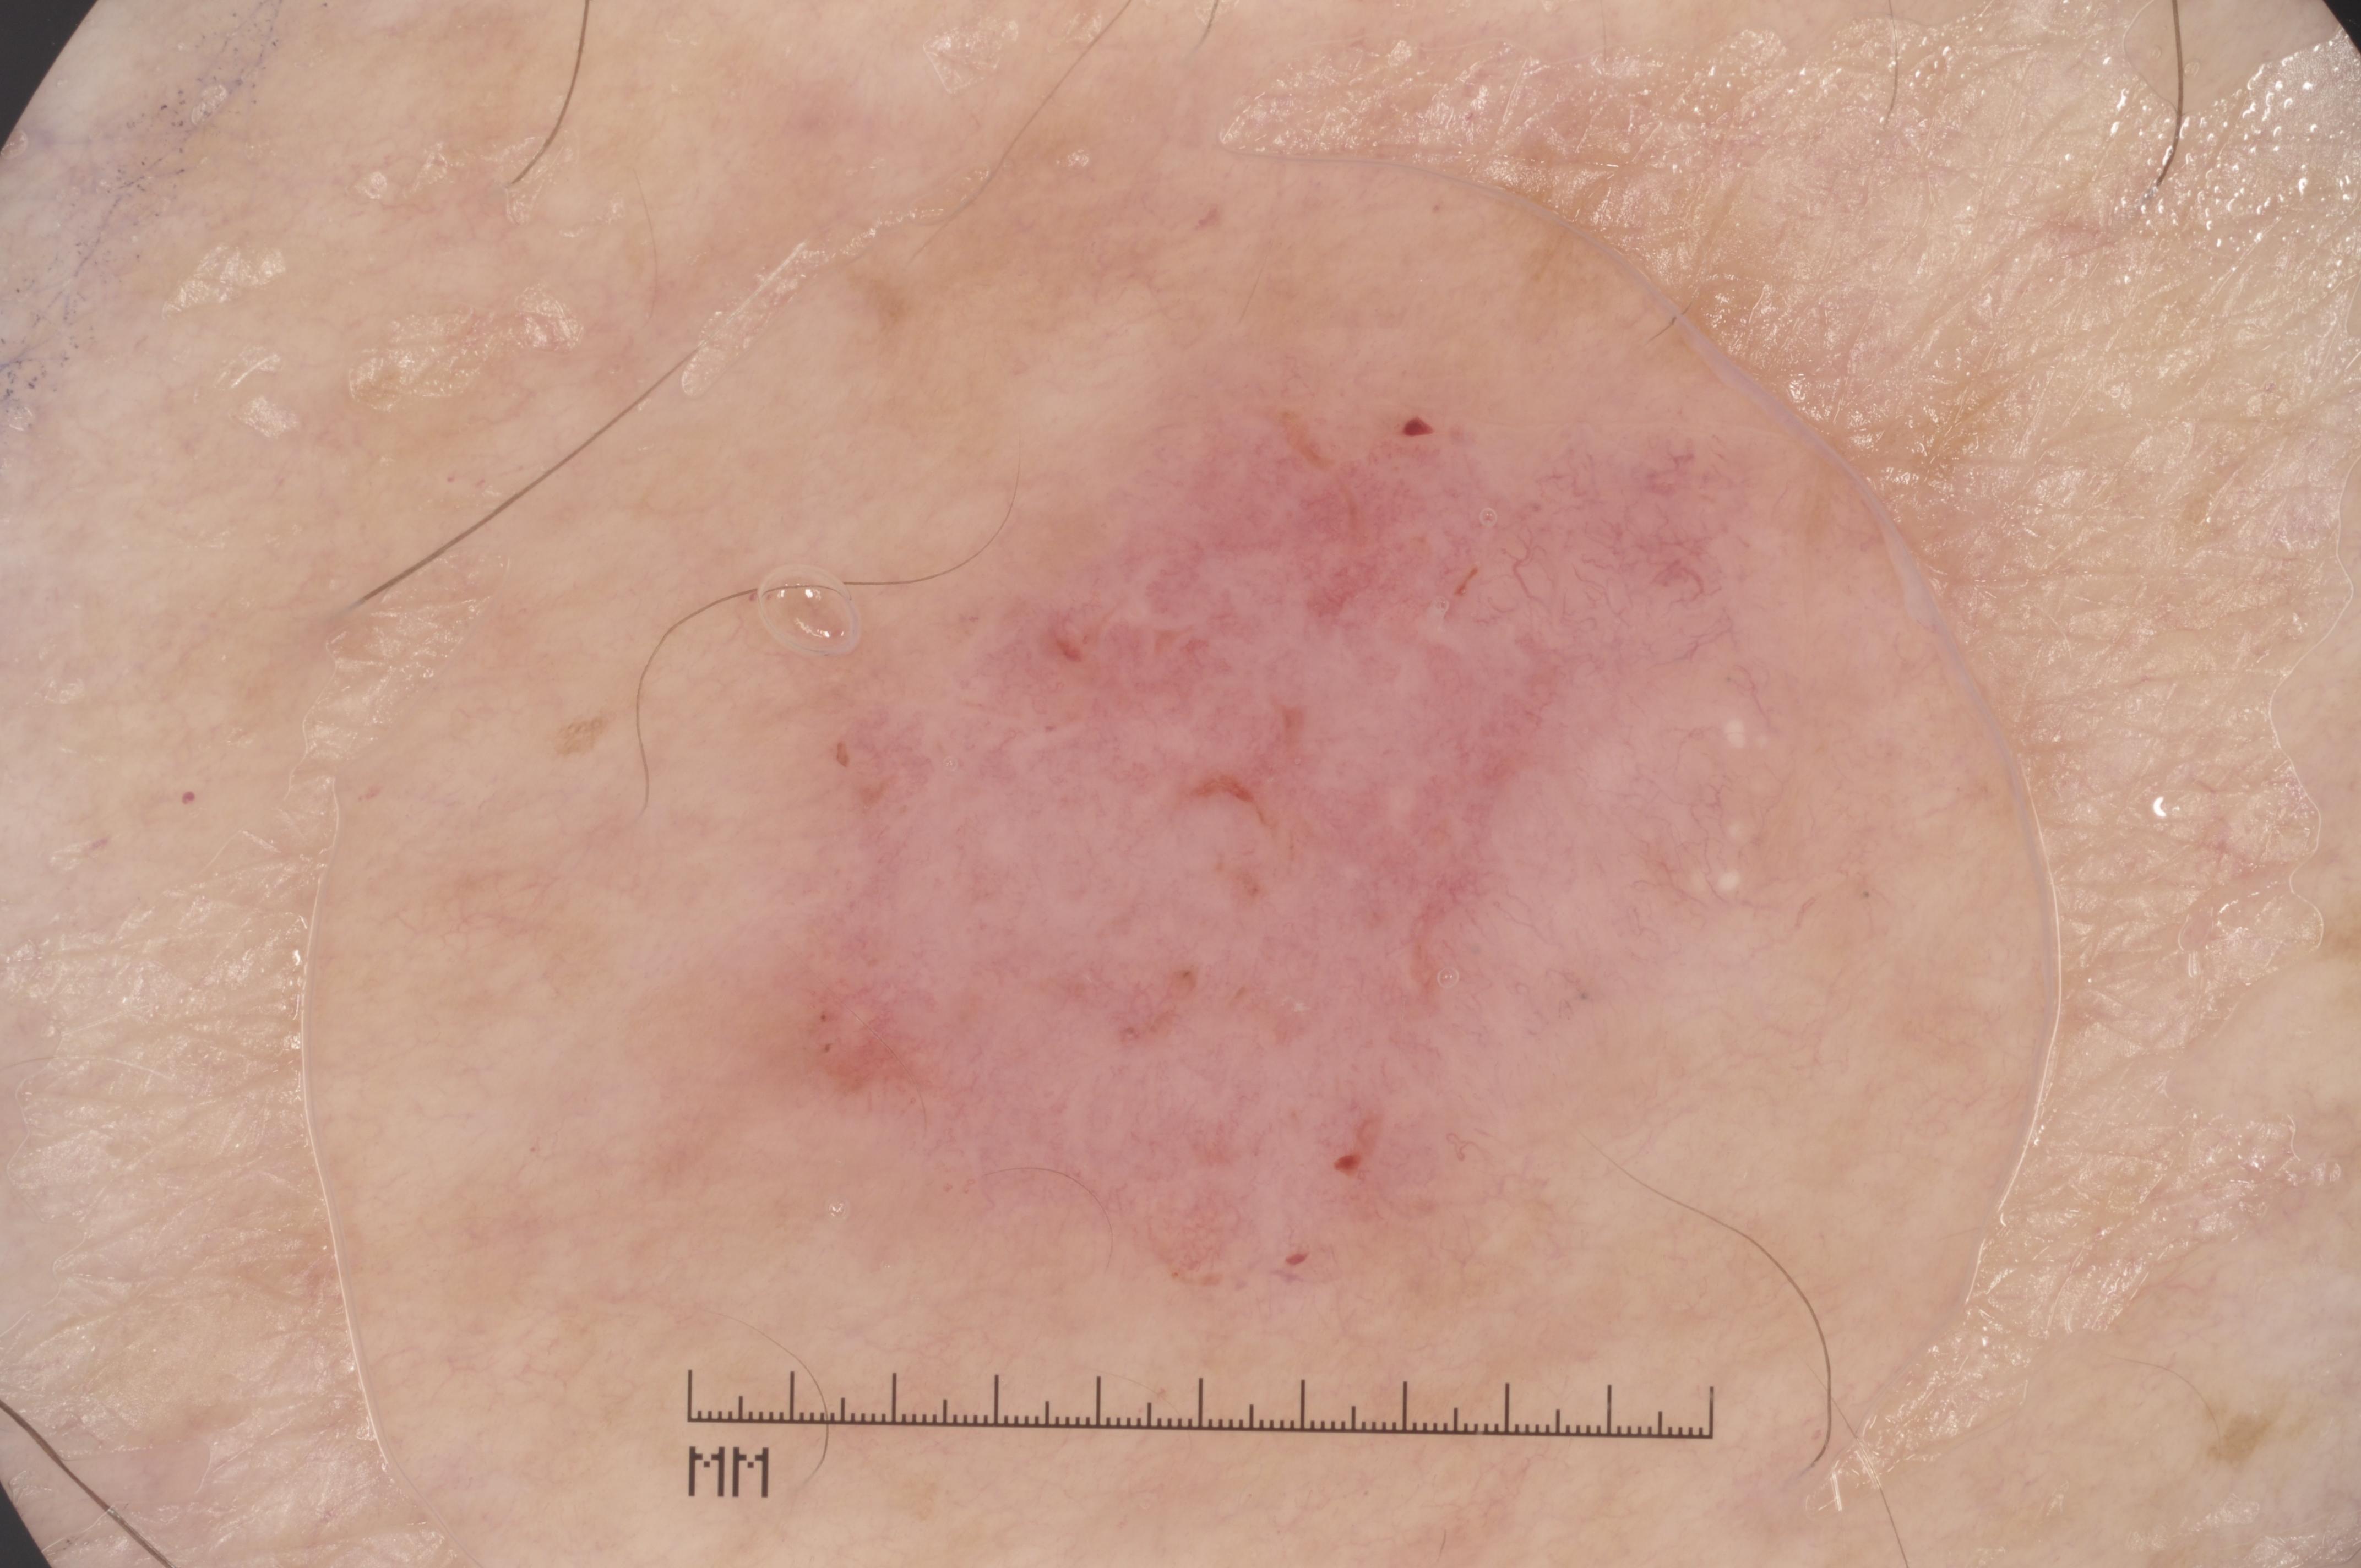

{

"age_approx": 40,

"anatom_site_general": "lower extremity",

"concomitant_biopsy": true,

"dermoscopic_type": "contact non-polarized",

"diagnosis_1": "Benign",

"diagnosis_2": "Benign melanocytic proliferations",

"diagnosis_3": "Nevus",

"diagnosis_confirm_type": "histopathology",

"image_type": "dermoscopic",

"lesion_id": "IL_0404349",

"melanocytic": true,

"sex": "female"

}